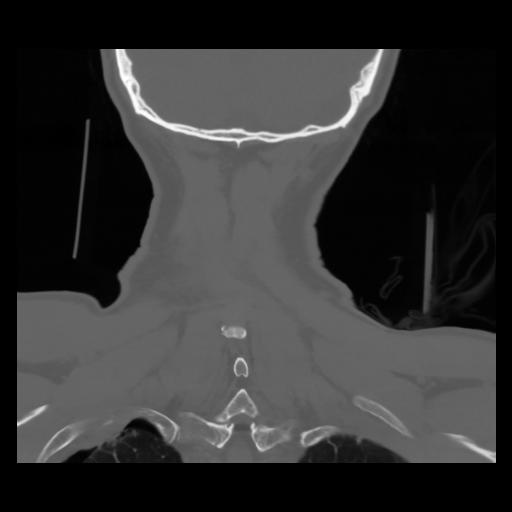

13 P.BLANDAS,,Coronal,2.000,P.BLANDAS,Coronal,